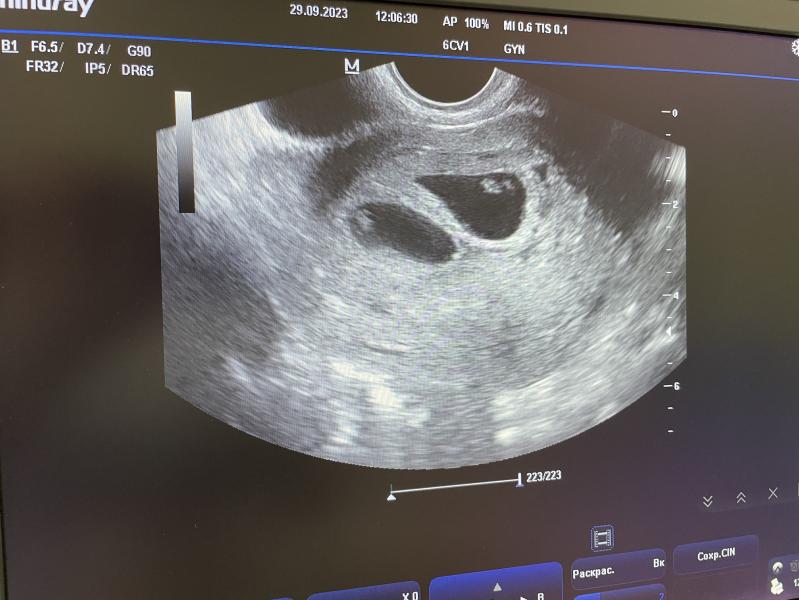

Мое первое узи)

Поздравляю! Такое же УЗИ шокоривало в феврале, а сейчас лежат сопят рядышком)

Поздравляю.У вас очень хорошая двойня,каждый малыш в своем домике,так что все будет хорошо.У меня обе в одном домике сидели,но ничего прошли через беременность чуток сложную, КС и вон уже им два года